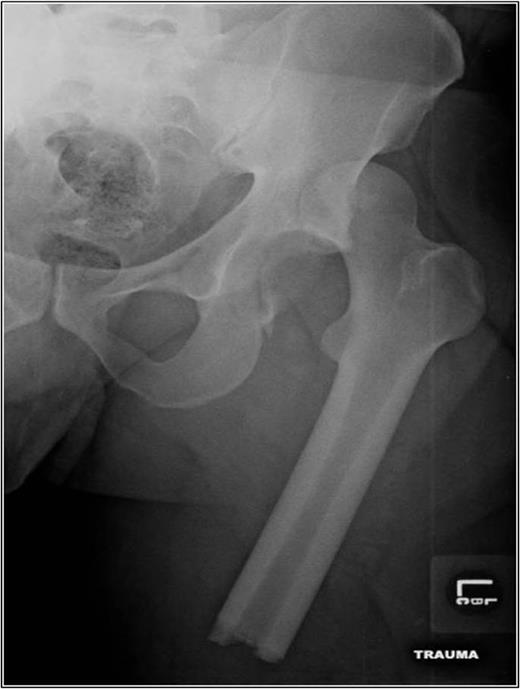

A 35-year-old male was involved in a high-speed urban dirt biking accident. The patient was stable with a GCS of 15 and was neurovascularly intact. His left knee exhibited a 10 × 20 cm medial traumatic arthrotomy and his thigh compartments were soft and compressible. Imaging revealed a left hip postero-superior dislocation, posterior wall acetabular fracture, ipsilateral transverse femoral diaphyseal fracture and an engaging hill-sachs-type lesion of the femoral head with the postero-superior acetabulum (Figs 1–3). Cefazolin, gentamicin and tetanus prophylaxis were administered along with a bedside washout of the traumatic arthrotomy. The patient was medically cleared for operative intervention as all blood work and further imaging were normal.

Coronal and axial CT pelvis of the left femoral head engaging with the postero-superior acetabulum.